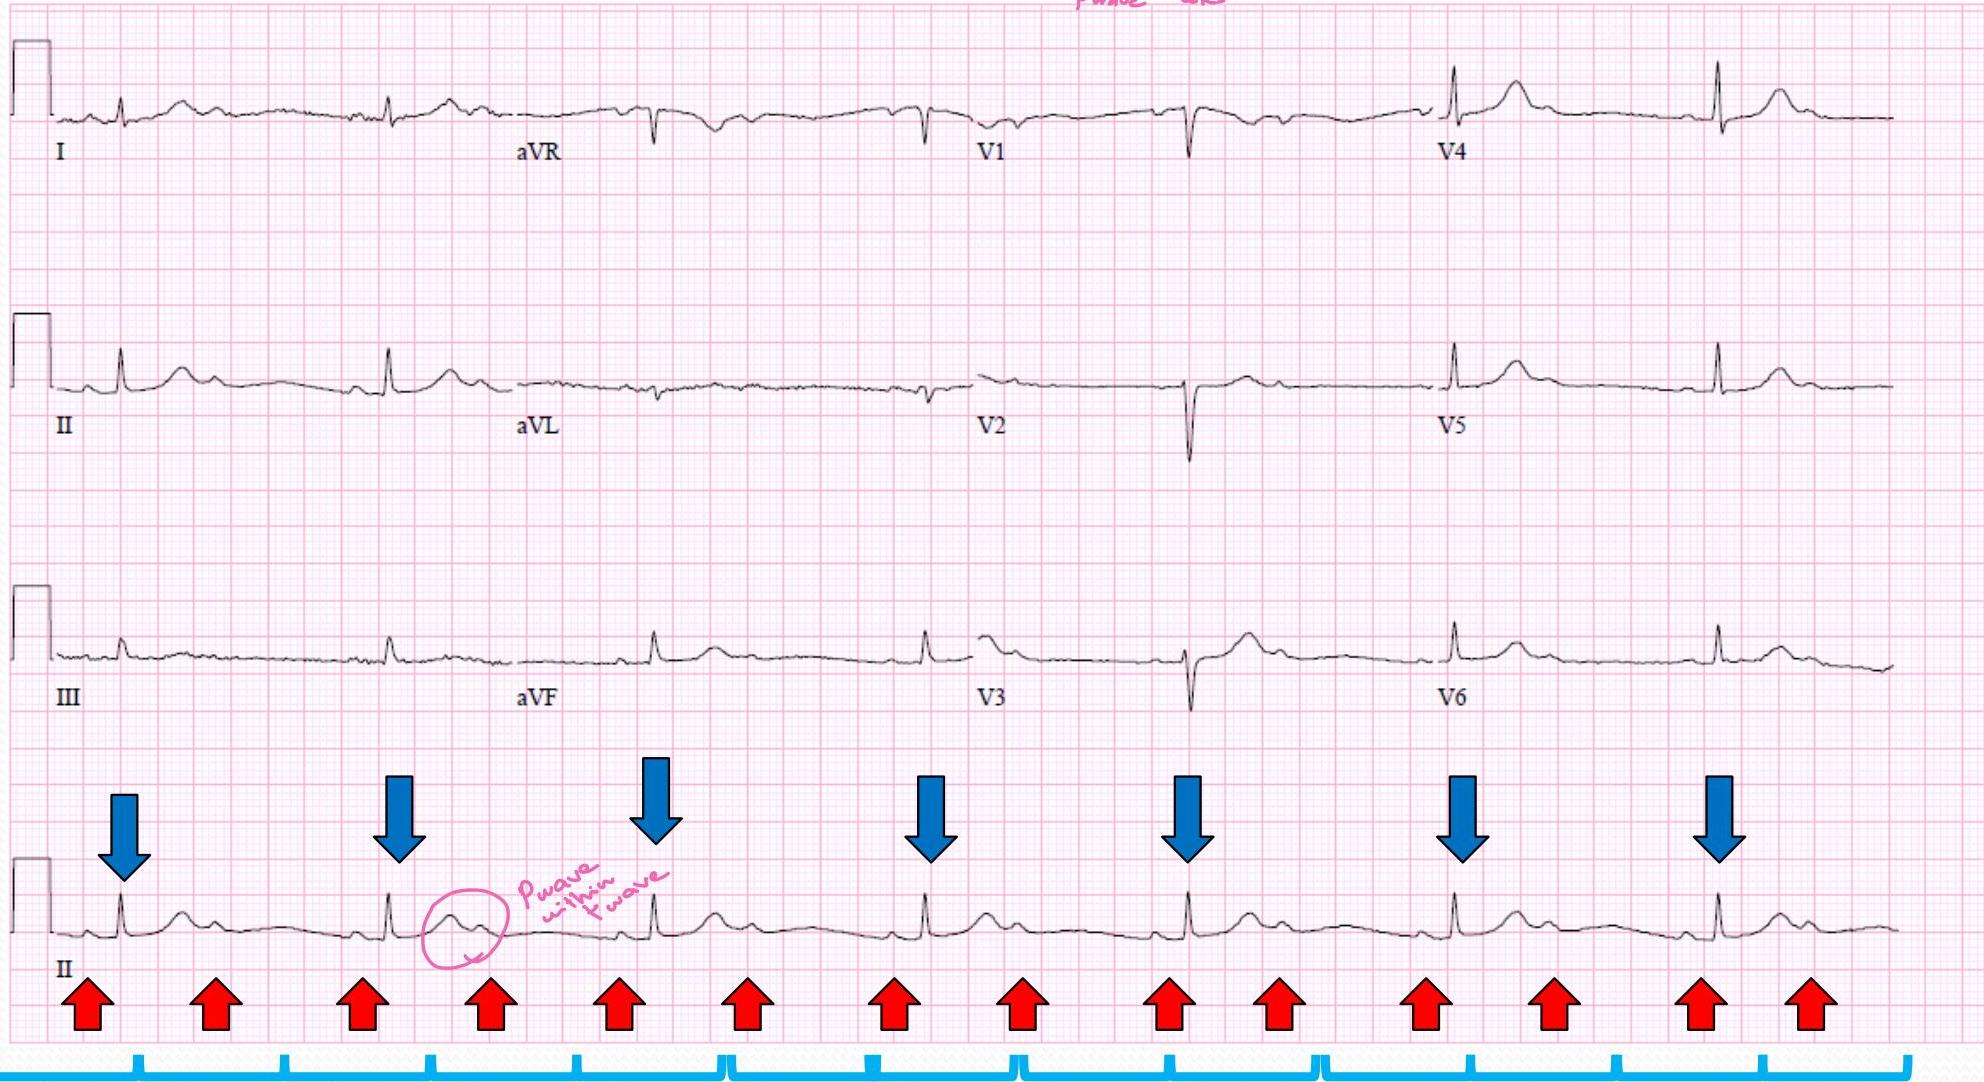

Long QT Syndrome (Jervell-Nielson-Lange)

Causes:

- hypothyroidism

- ↓ mg⁺ ↓ Ca⁺ ↓ Na⁺

- macrolides “Erythromycin”

- Glucosamine “sokimalarina”

Congenital:

- ↓ subba Death

- ↓ Definess

**QT

(sec)

- significant

-

450 m sec is